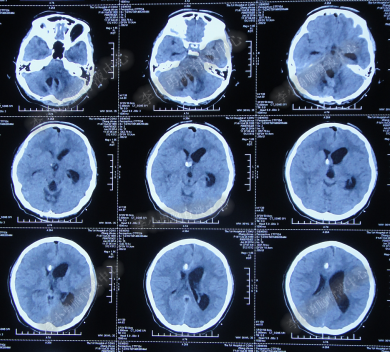

2014年8月31日住入李小勇脑脊液中心,入院时:卧床,表情淡漠,神志嗜睡;体温高37.9°C;头颅枕后正中手术瘢痕,结痂尚未脱落;左枕侧脑室外引流固定在位,尚通畅,可见淡红色浑浊脑脊液引出;颈抵抗,双肺呼吸音粗(图-27);头部CT检查示(小脑肿瘤术后颅内感染病例)脑室系统粘连严重伴双侧颞角脑室扩张明显,双侧侧脑室见引流管影,脑内见多发斑片低密度,中线结构无移位,颅骨术后改变(图-28)。

图-27:2014年8月31日入院时

图-28:2014年8月31日头部CT

入院第4天即2014年9月3日,左枕脑室外引流管引流脑脊液量不多,晨起4:00左右出现血压升高伴瞳孔扩大,4.5:2.0;多参数生理:心率102次/分,呼吸11次/分,血压141/96mmHg,血氧饱和度98%;急行头部CT检查示双侧侧脑室扩大,颞角扩张显著,双侧侧脑室见引流管影,位置变化不大,脑内见多发斑片低密度(图-29)。

图-29:2014年9月3日4点50分头部CT